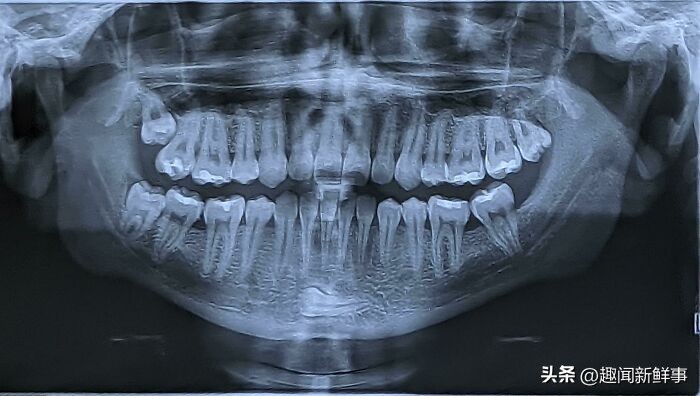

34.发现下巴上藏有一颗牙齿